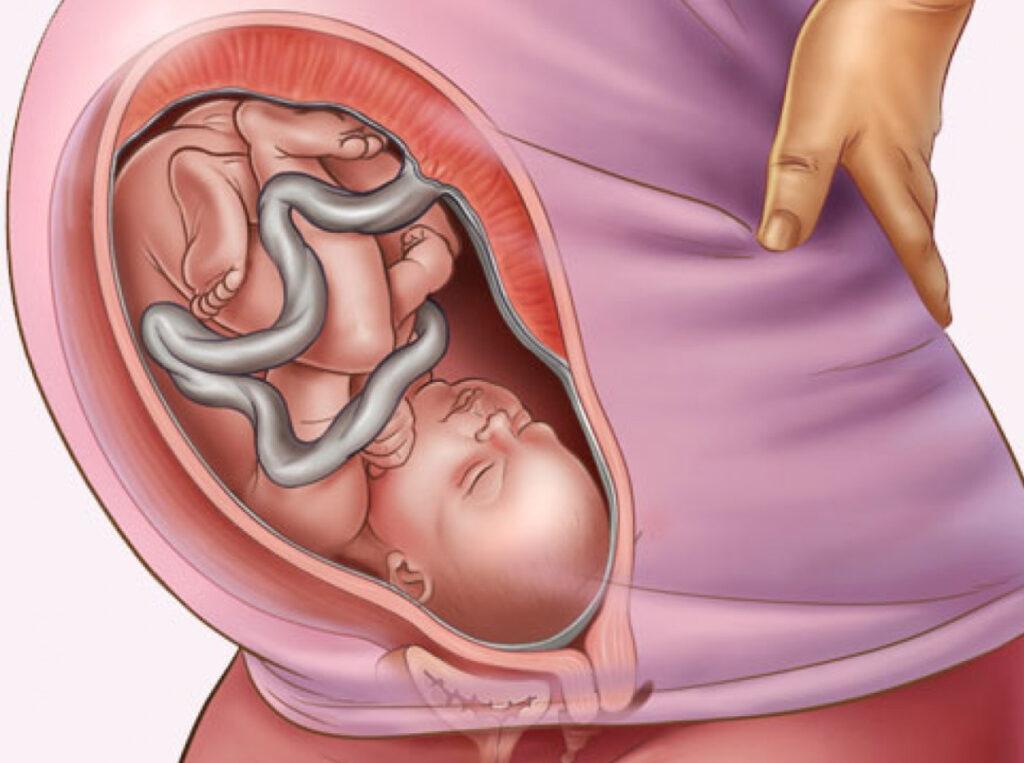

Плод 39 Недель Фото

Плод 39 Недель Фото 100 фото